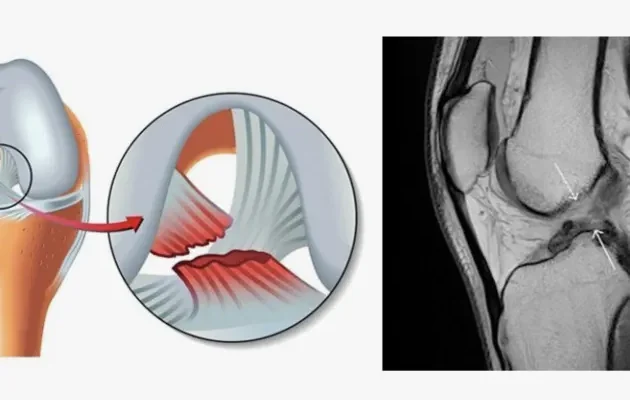

Çapraz bağ yırtığı, diz ekleminin stabilitesini sağlayan ön veya arka çapraz bağlardan birinin tamamen veya kısmen yırtılması durumudur. Dizdeki bu bağlar, bacak kemiklerinin birbirine doğru şekilde bağlanmasını sağlar.

Çapraz bağ yırtığının teşhisi için uzman hekimler tarafından yapılan klinik muayene büyük önem taşır. Muayene sırasında dizin stabilitesi, hareket kabiliyeti ve ağrı noktaları değerlendirilir. Ancak, kesin teşhis için görüntüleme tekniklerine ihtiyaç duyulur. Radyolojik incelemeler, yırtığın boyutunu ve yerini belirlemede kritik rol oynar.

Çapraz bağ yırtığının tanısında radyolojik görüntüleme yöntemleri büyük önem taşır. Diz ekleminin yapısını en detaylı şekilde inceleyebilmek için genellikle diz mr kullanılır. Özellikle, yüksek çözünürlüklü Diz mr, çapraz bağ yırtığının teşhisinde en etkili yöntemlerden biridir. Bu cihazlar, bağ dokularının net bir şekilde görüntülenmesine olanak tanır ve yırtığın derecesini belirlemekte kritik rol oynar.